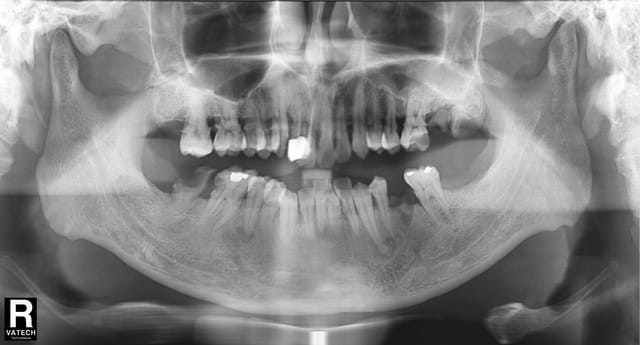

Ce patient de 45 ans presente, entre autre, une lesion a l'apex de 33 et 34.

Notez la modification du trajet du nerf dentaire inferieur.

ça ressemble à un truc tummeur odontogène ou osseuse bénigne du genre petit fibrome cémento-ossifiant.

Par contre ton canal n'est pas dévié à mon sens, il est comme il est, sans particularité.

Pour le canal, il me semble que les trabeculations osseuses autour de "la chose"-ome sont concentriques et repousse le nerf.

Par comparaison le coté droit semble tt a fait normal, meme si la nature n'aime pas la symetrie... C juste une impression.

sinon ça ressemble aussi à une simple dysplasie cémentaire périapicale.

J'aimerais juste savoir si la 33 est très abrasée en occlusal comme la pano pourrais le laisser croire (dans ce cas je pense que le diagnostic de nécrose aseptique est encore plus probable). Sino, que donnent les tests au froid et l'analyse occlusale ?